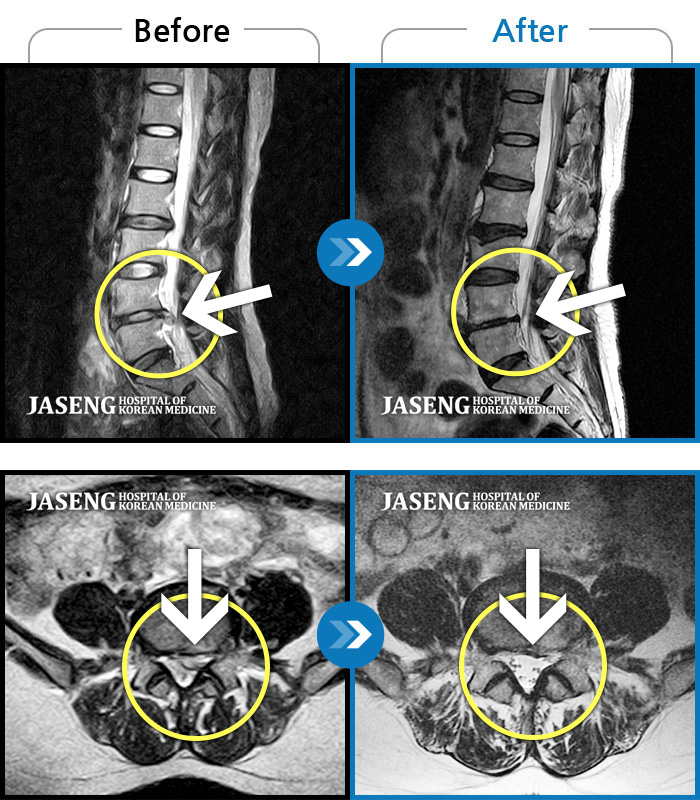

MRI로 보는 치료결과

1,169건의 MRI 전후 사진으로

터진 디스크 흡수 사례를 확인하세요.

[촬영시기:23.02.03~24.02.14]

[촬영시기:23.02.03~24.02.14]

[수원_허리디스크] 허리 통증과 좌측 대퇴부 저림과 당김조회수 0 2024.11.21 -